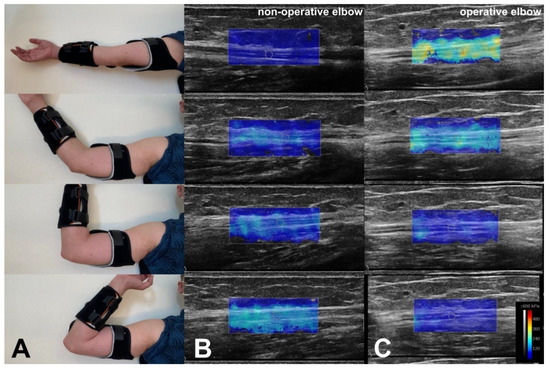

| Case | Sex | Age (y) | Operated Side | Grade (McGowan) | Motor Ulnar Nerve Conduction Velocity (m/s) Amplitude (µV) | Time between Surgery and SWE (Months) | Distance Ulnar Nerve/Medial Epicondyle after Transposition (cm) | Shear Elastic Modulus of the Ulnar Nerve (kPa) Non-Operated Side. Elbow Flexion: 0° 45° 90° 120° | Shear Elastic Modulus of the Ulnar Nerve (kPa) Operated Side. Elbow Flexion: 0° 45° 90° 120° |

|---|---|---|---|---|---|---|---|---|---|

| 1 | male | 78 | R | 2 | 26 3.9 | 12 | 1.2 | 38.2 30 41.3 82.3 | 116.2 86.5 66.6 38.9 |

| 2 | male | 41 | L | 2 | 35.2 6.9 | 7 | 1.0 | 27.9 38.8 96.8 146.0 | 150.1 137.0 91.1 58.5 |

| 3 | female | 25 | L | 2 | 23 14.4 | 9 | 1.1 | 29.9 92.9 123.2 140.7 | 260.7 178.6 80.6 60.9 |

| 4 | male | 43 | R | 1 | 40 6.8 | 18 | 1.0 | 37.1 86.1 105.5 145.7 | 165.7 143.3 87.9 52.8 |

| 5 | female | 53 | R | 2 | 37 8.1 | 3 | 0.49 | 54.6 56 70.2 157.4 | 72 56.1 29 49.6 |

| 6 | female | 68 | R | 2 | 11 5.2 | 2 | 1.23 | 38 65 88.1 140.7 | 178.5 126.4 55.7 26.9 |

| 7 | female | 53 | L | 2 | 40 9.8 | 16 | 0.65 | 47.8 139.1 144.7 156.3 | 202.6 146.1 110.7 67.5 |

| 8 | male | 40 | L | 3 | ---- | 3 | 2.13 | 39.9 35.2 95.4 111.6 | 115.8 62.1 72.5 53 |

| 9 | male | 56 | L | 3 | ---- | 3 | 1.2 | 35 79.6 122.4 173.5 | 160.7 70.7 70.2 62.4 |

| 10 | female | 69 | R | 1 | 40 5.1 | 3 | 1.33 | 20.6 36.5 57.5 108.5 | 129.7 100.7 50.5 16.6 |

| 11 | male | 49 | L | 1 | 32 6.5 | 12 | 2.04 | 39.4 92.8 115.2 196.3 | 174.5 151.5 102.8 34.8 |